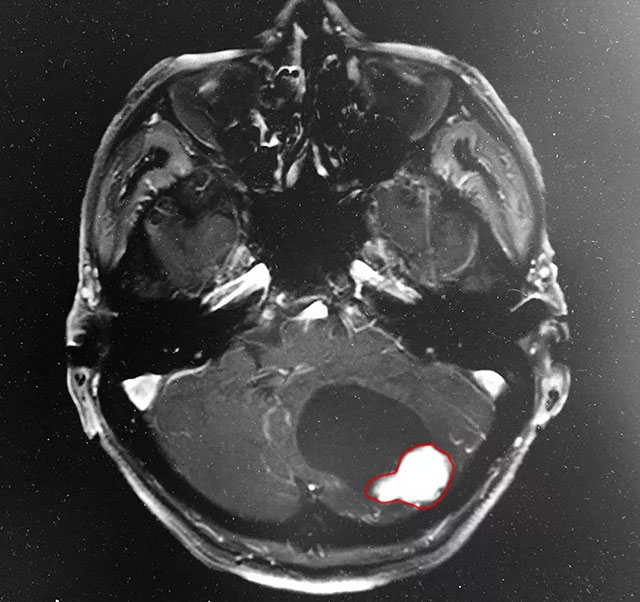

为了进一步明确病因,吴主任建议患者增强扫描:头颅MRI平扫+增强+DWI+MRA,影像学结果提示:患者为良性的小脑肿瘤,同时结合患者病情、病症和病史,考虑为血管母细胞瘤可能性很大。

▲ MRI影像显示:患者为小脑肿瘤

据吴博士介绍,患者的小脑肿瘤为良性——这算是不幸中的万幸。但他当时的情况还是很严重的,由于肿瘤压迫,脑部水肿情况比较明显,第四脑室受压变形,导水管与脑池也受压,双侧侧脑室及第三脑室明显扩大,颅底中线结构向左侧偏移。为了患者更好的治疗,吴博士特邀神经外科特需专家李士其教授进行会诊,经过商量讨论,他们一致认为患者头痛、恶心、走路不稳症状严重,手术指征明显,应尽早手术。